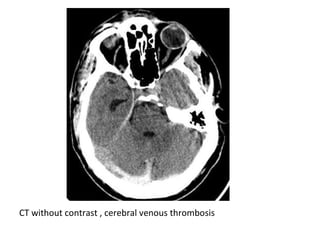

CT without contrast , cerebral venous thrombosis

CT without contrast , cerebral venous sinus thrombosis